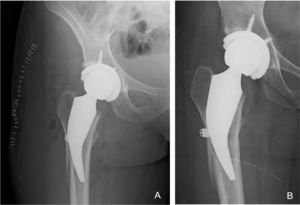

Complications and revisions: five cases of fracture were detected intraoperatively, four in the proximal calcar region (incomplete) which were treated with wire cerclage during the same primary surgery (one progressed to loosening and had to be revised two years after surgery [1.1% of the series]) and one case with fracture of the lateral cortex in a patient with pronounced coxa valga which was also treated with wire cerclage in the same surgical act as the primary replacement. Consolidation of the lateral cortex fracture was before three months and did not progress to loosening. Walking with a walker was only limited for the first 45 days (Fig.2) was allowed. All intraoperative fracture cases were within the first 30 cases performed with this implant. Postoperatively, there was one case of traumatic dislocation which was resolved with closed reduction, and one superficial surgical wound infection which resolved with medical and antibiotic treatment (Table 2).

The image shows a woman aged 32 years who underwent a THA for osteonecrosis of the right hip. A) Postoperative X-ray of the same patient with THR with cortical fracture of intraoperative lateral femoral cortex treated during surgery with monofilament twisted wire cerclage. B) AP X-ray showing a well-fixed stem with no subsidence and a consolidated lateral femoral cortex and good fixation at six months follow-up.